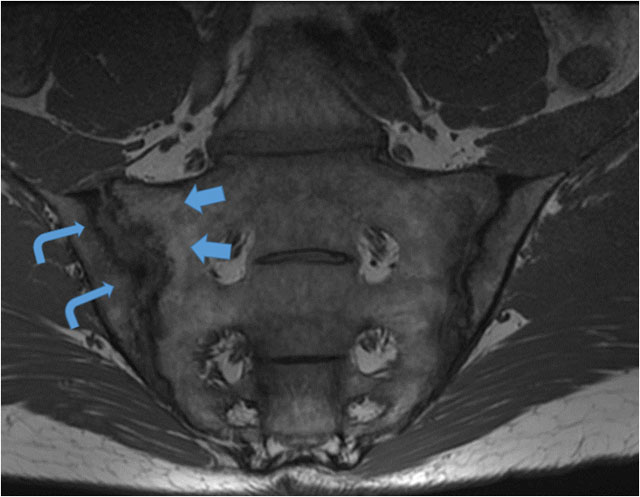

Figure 1

T1-W mid coronal oblique image through the SIJ in a 42-year-old male who presented with long standing low back pain, raised inflammatory markers and a positive HLAB27. Juxta-articular geographical fat infiltration (blue arrows) is noted as structural lesions, along the sacral margin of the SIJ. Pseudowidening of the joint on MRI with large elongated erosions along the iliac aspect and subarticular sclerosis (curved arrowheads) of the right SIJ.